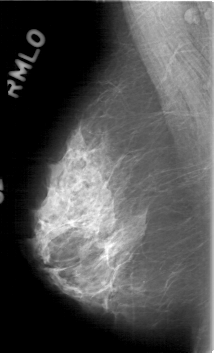

D_4088_1.RIGHT_MLO

RIGHT_MLO LINES 5281 PIXELS_PER_LINE 3196 BITS_PER_PIXEL 12 RESOLUTION 43.5 NON_OVERLAY